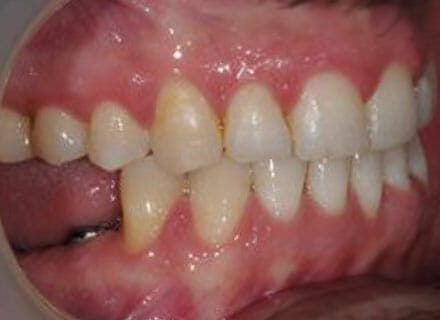

Big gaps and missing back teeth

This is a case where orthodontics and dental implants were used. First we closed the big gaps at the front using a fixed clear brace (this took under 12 months. Then we added 2 new teeth on the lower right where the premolar and molar were decayed right through using dental implants. Here the after pics were taken before the new implant teeth were added lower right.